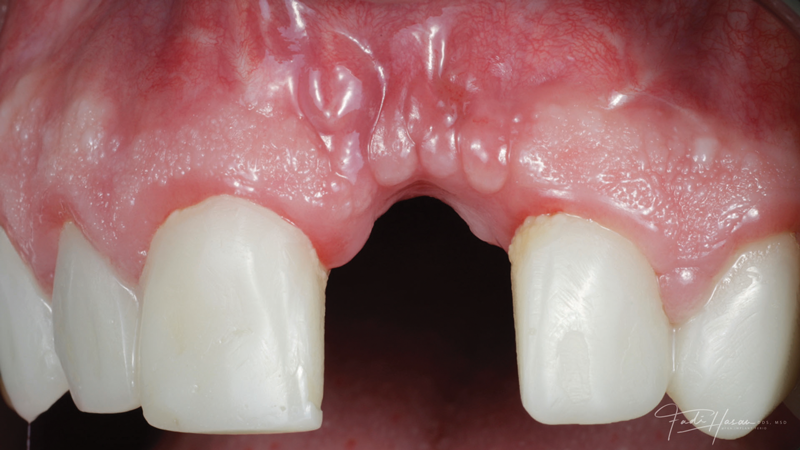

(11.) Preoperative close-up view of the tooth No. 9 site following implant placement and a period of healing, exhibiting a residual soft-tissue deficiency and an undulating facial soft-tissue morphology.

Figure 11

A patient presented for the restoration of an implant that had been placed at the site of tooth No. 9, which exhibited a residual soft-tissue deficiency and an undulating facial soft-tissue morphology (Figure 11). The objective of the treatment was to change the appearance and thickness of the facial soft tissue prior to crown placement to optimize the esthetics and prevent future soft-tissue dehiscence. After flap reflection (Figure 12), a graft was acquired from the patient's tuberosity to augment the supracrestal soft tissue (Figure 13). A volume-stable collagen matrix was then placed to further increase the thickness of the soft tissue adjacent to the implant body (Figure 14), and the flap was sutured closed (Figure 15). Following a 3-month healing period, a positive change in the soft tissue's morphology was apparent; however, its volume remained deficient when compared with that of tooth No. 8 (Figure 16). When the screw-retained crown was delivered, a second graft was acquired from the tuberosity and placed to further increase the volume of the supracrestal soft tissue (Figure 17 and Figure 18). A postoperative healing period of 4 months resulted in an ideal position of the margin of tooth No. 9 with regard to its contralateral counterpart as well as more natural looking soft-tissue morphology and excellent supracrestal soft-tissue thickness (Figure 19 and Figure 20). Eight months postoperatively, the position of the gingival margin and the thickness of the soft tissue had been maintained (Figure 21 and Figure 22).